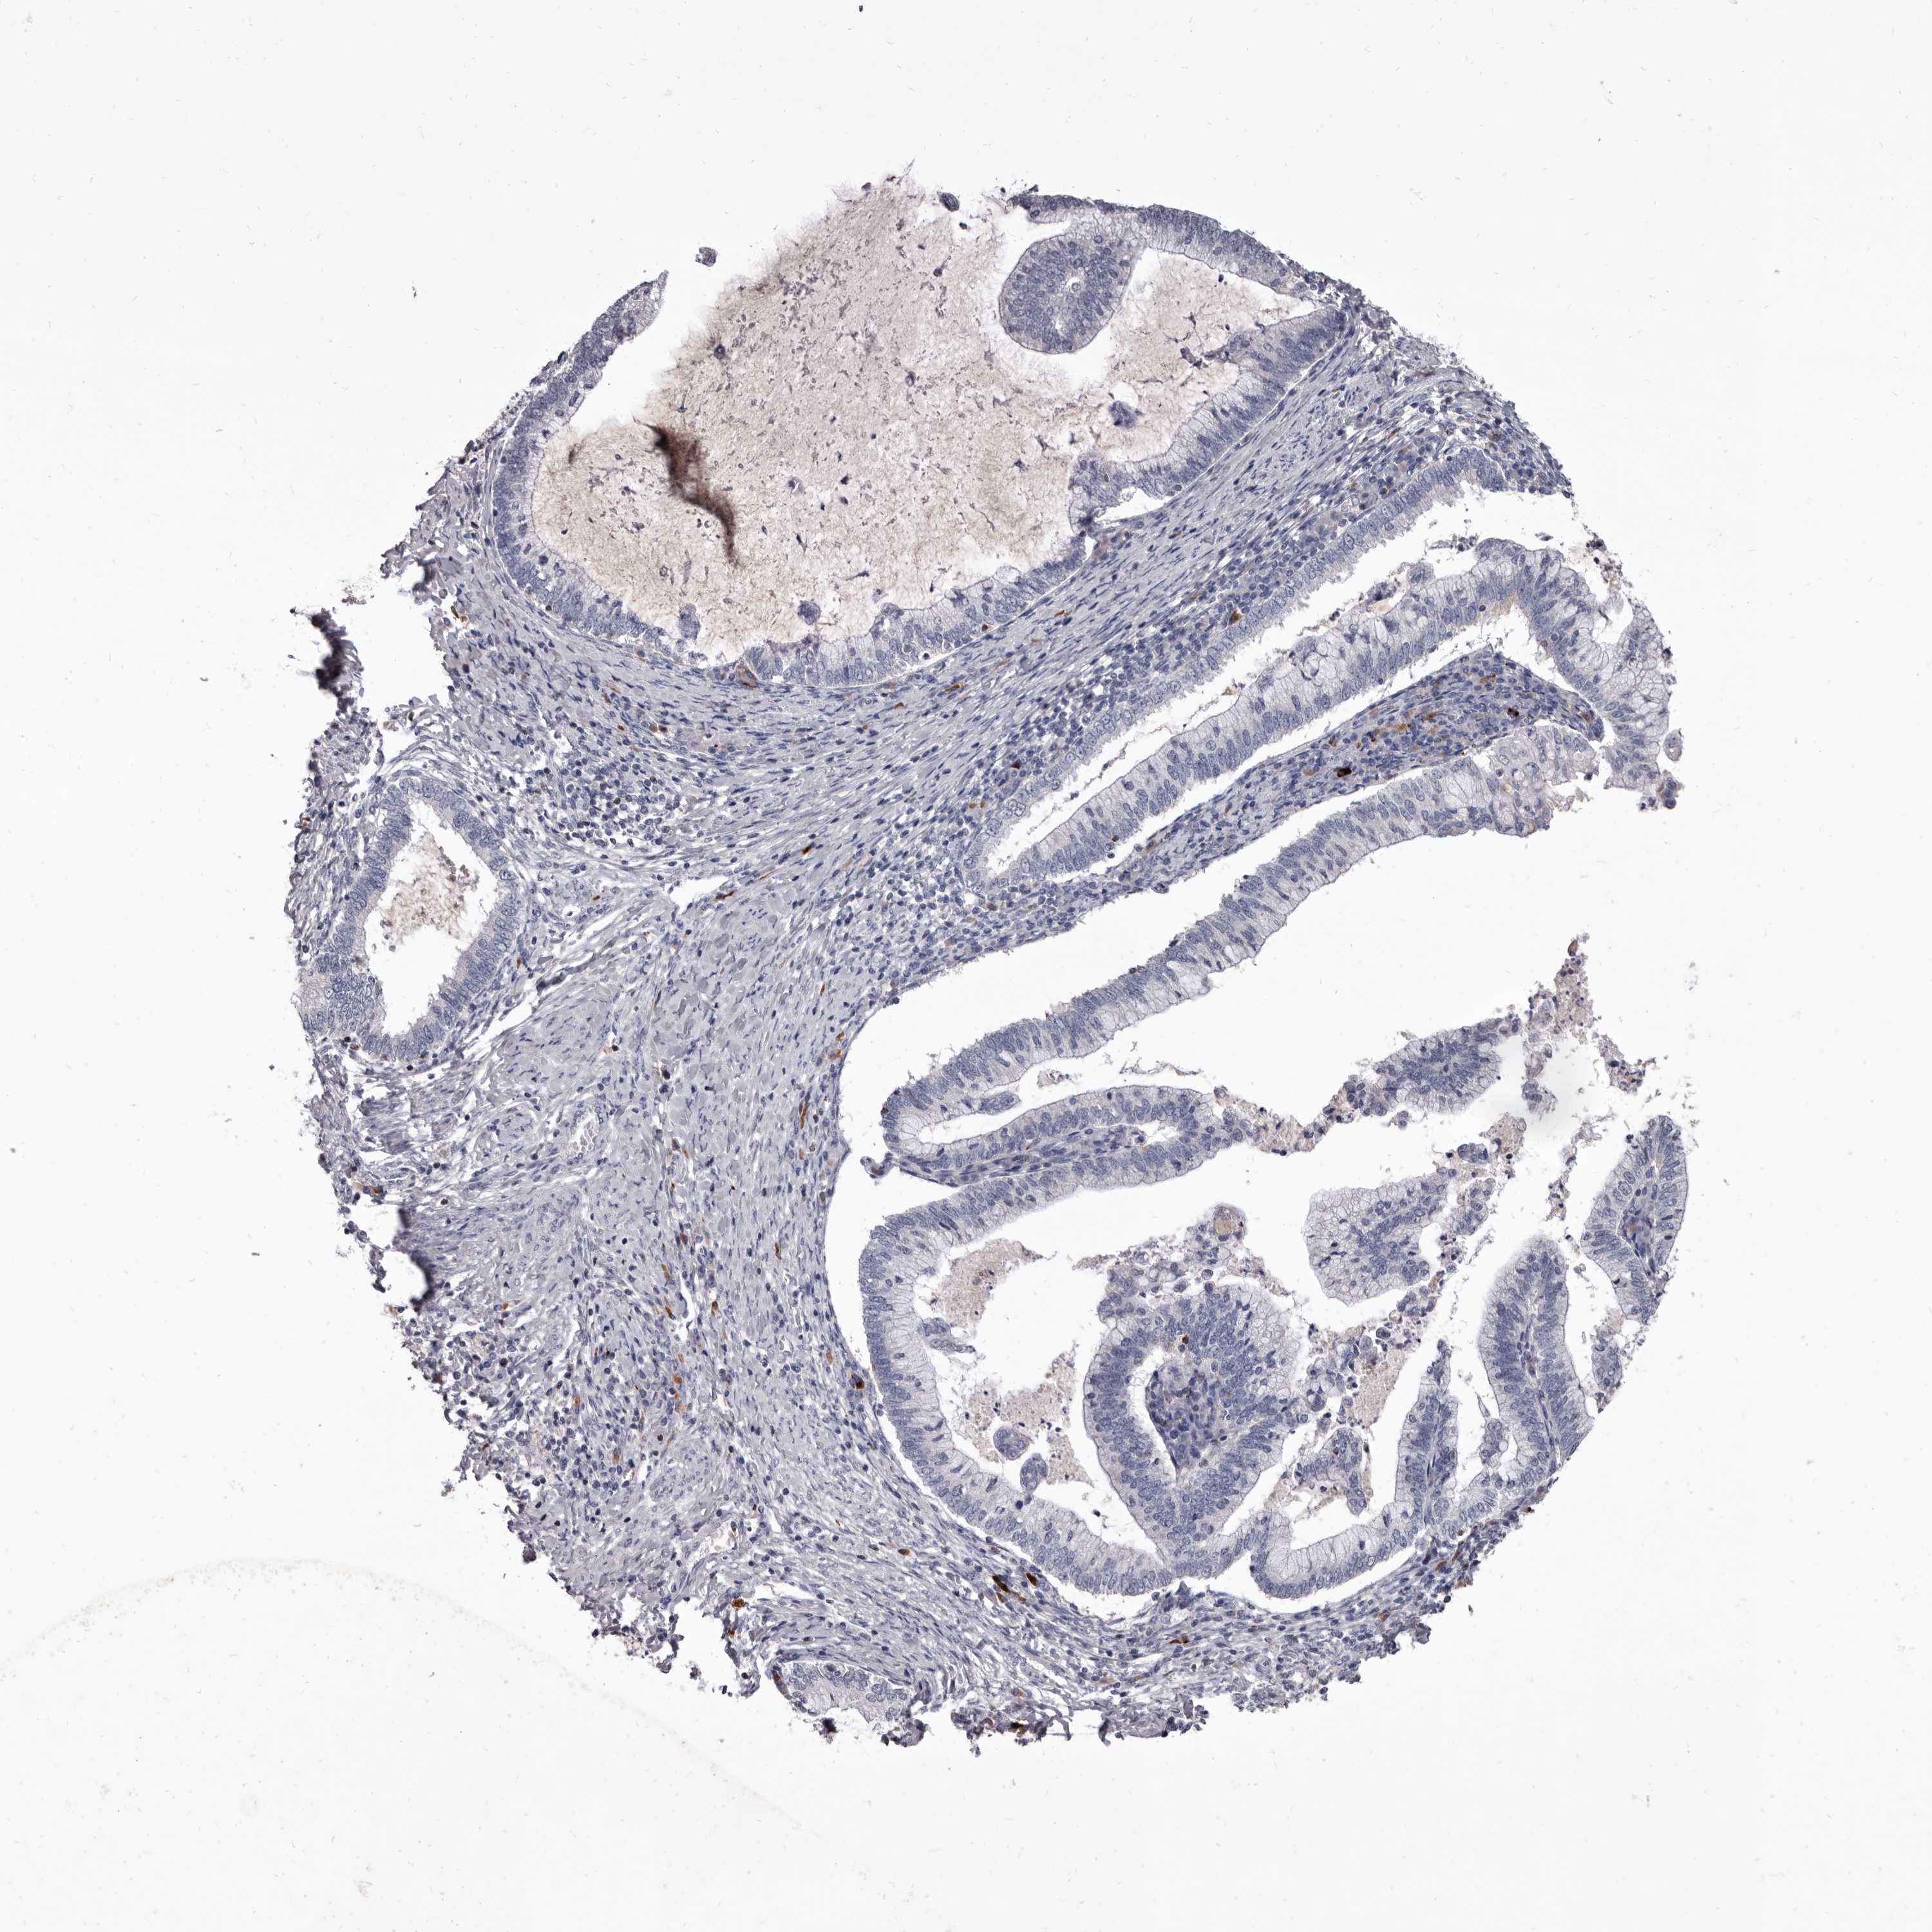

CERVICAL CANCER - Protein expressioni

A mouse-over function shows sample information and annotation data. Click on an image to view it in a full screen mode. Samples can be filtered based on level of antibody staining by selecting one or several of the following categories: high, medium, low and not detected. The assay and annotation is described here.

Note that samples used for immunohistochemistry by the Human Protein Atlas do not correspond to samples in the TCGA dataset.

Antibody stainingi

Antibody staining in the annotated cell types in the current human tissue is reported as not detected, low, medium, or high, based on conventional immunohistochemistry profiling in selected tissues. This score is based on the combination of the staining intensity and fraction of stained cells.

Each image is clickable and will lead to virtual microscopy that enables deeper exploration of all samples and also displays staining intensity scores, fraction scores and subcellular localization as well as patient and tissue information for each sample.

Antibody HPA029200

Staining

High

Medium

Low

Not detected

Intensity

Strong

Moderate

Weak

Negative

Quantity

>75%

75%-25%

<25%

None

Location

Nuclear

Cytoplasmic/membranous

Cytoplasmic/membranous,nuclear

Squamous cell carcinoma, NOS

Adenocarcinoma, NOS